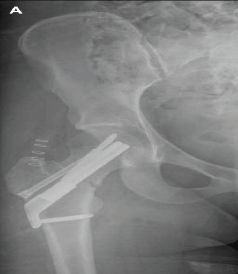

Total Hip Arthroplasty with Cage Application for Complex Posterior Hip Dislocation and Acetabular Fracture in a Patient with Prior Patellectomy: A Case Report

Amit Saraf , Sandeep Bishnoi , S Krishna Kumar